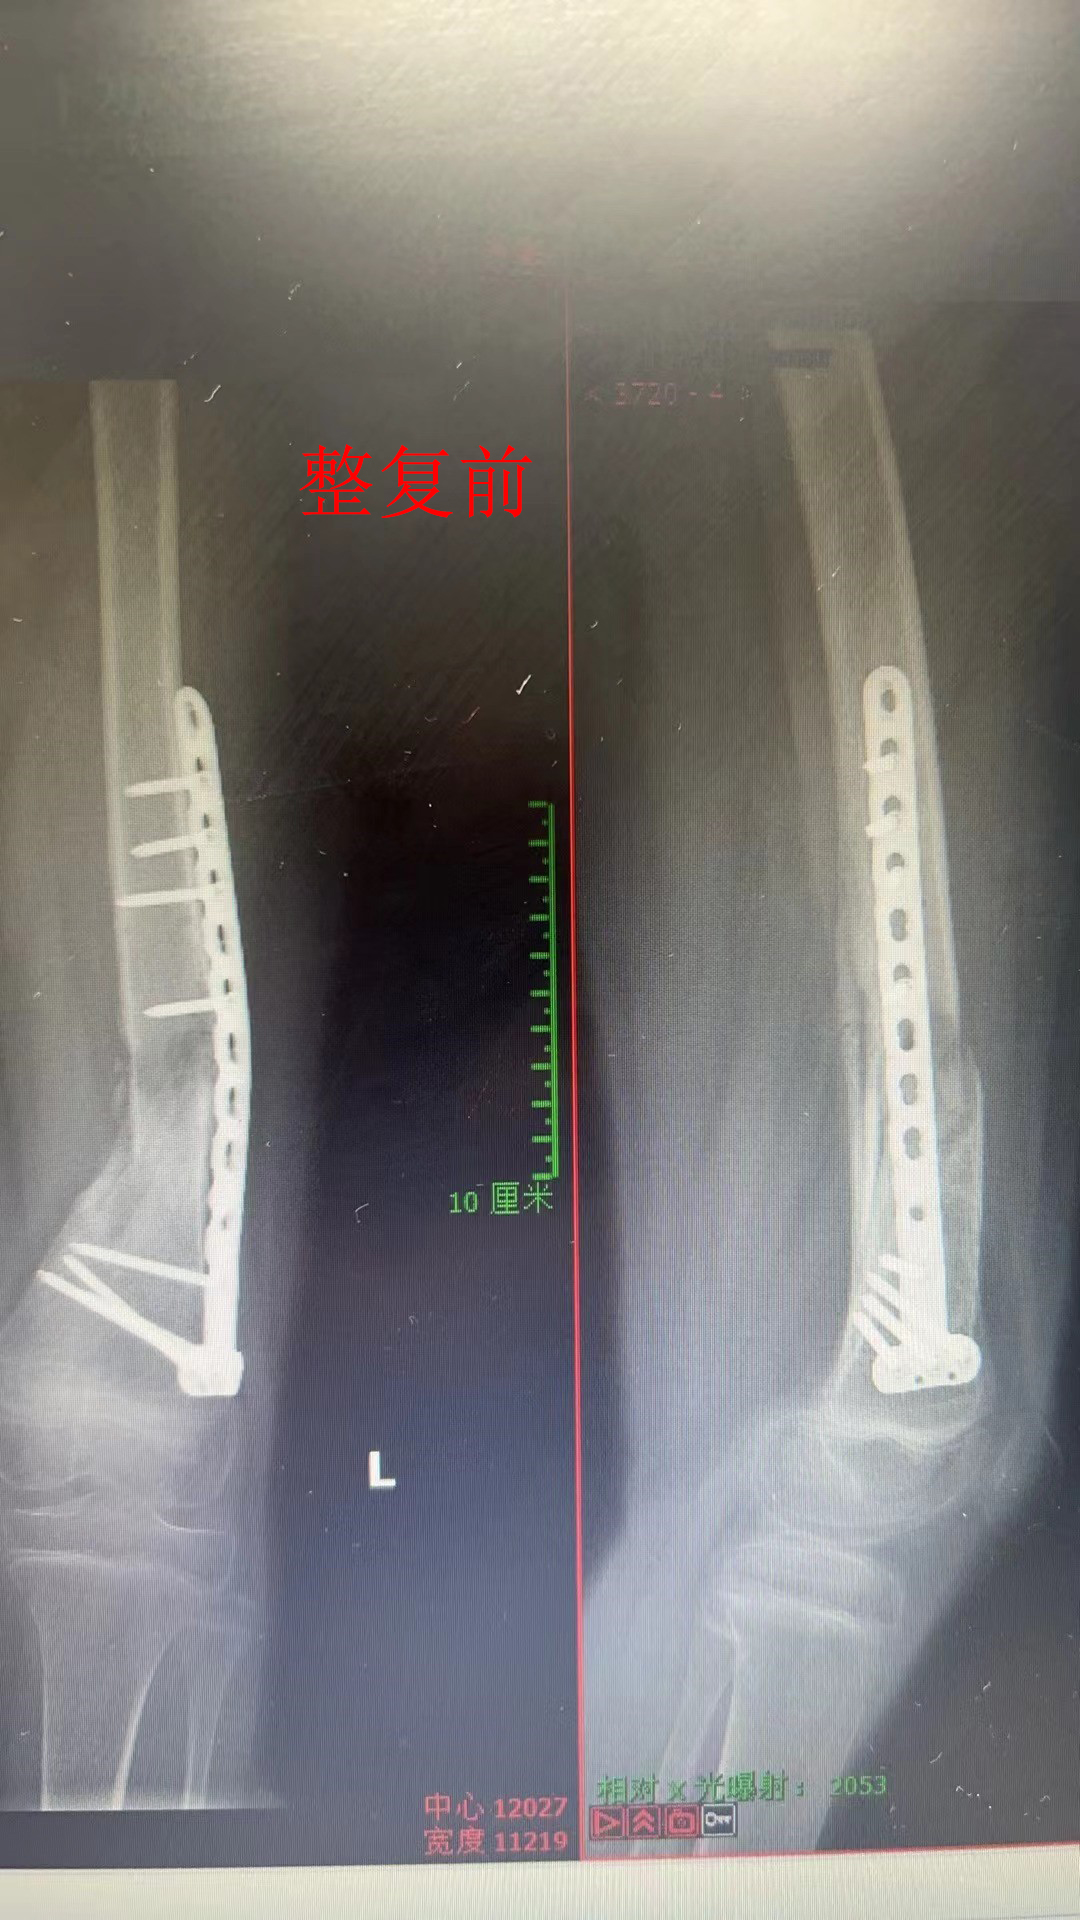

这对夫妻的10岁女儿,4个月前不幸遭遇车祸导致左侧大腿骨折,车祸后在当地医院手术,但术后效果不良,骨折处不愈合,并且钢板弯曲,下肢畸形,当地医院建议再次手术取出钢板,髋部取骨填充断端。家长百愁莫展,不仅孩子学业中断,而且腿部20厘米长的手术疤痕使孩子感到恐惧,万般无奈之下一家人先后到郑州多家大型医院就诊,却均被建议手术。最后,家属抱着一丝希望到我院求诊,孩子妈妈对着万富安主任说:“能不手术最好,如果必须做手术,还是要到咱洛阳正骨医院做。”

面对家属的信任,万富安主任团队精心为患儿设计治疗方案,在透视下与吕秉舒医生通过手法整复复位,使患儿骨折钢板复位良好。看到患儿一家人竖起的大拇指,万主任和他的团队感到由衷的欣慰。整复后,为患儿使用髋人字石膏固定,护士长带领护理团队精心照顾,患儿一天天康复,露出久违的笑脸。临出院这天,患儿家长送上锦旗和感谢信,紧紧握住医护人员的手,表达深深的谢意。